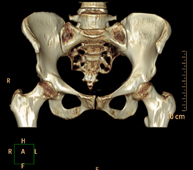

Exploració radiològica que mitjançant un sistema de raigs X i detectors que giren al voltant del pacient i que reconstrueixen les imatges per ordinador (TC Multidetector), permet l'estudi detallat dels ossos, els músculs i les articulacions de la mà i el canell. - TC de la pelvis òssia

Exploració radiològica que mitjançant un sistema de raigs X i detectors que giren al voltant del pacient i que reconstrueixen les imatges per ordinador (TC Multidetector), permet l'estudi detallat dels ossos, els músculs i les articulacions de la pelvis. - TC de malucs

Exploració radiològica que mitjançant un sistema de raigs X i detectors que giren al voltant del pacient i que reconstrueixen les imatges per ordinador (TC Multidetector), permet l'estudi detallat dels ossos, els músculs i les articulacions del maluc. - TC de sacroilíaques